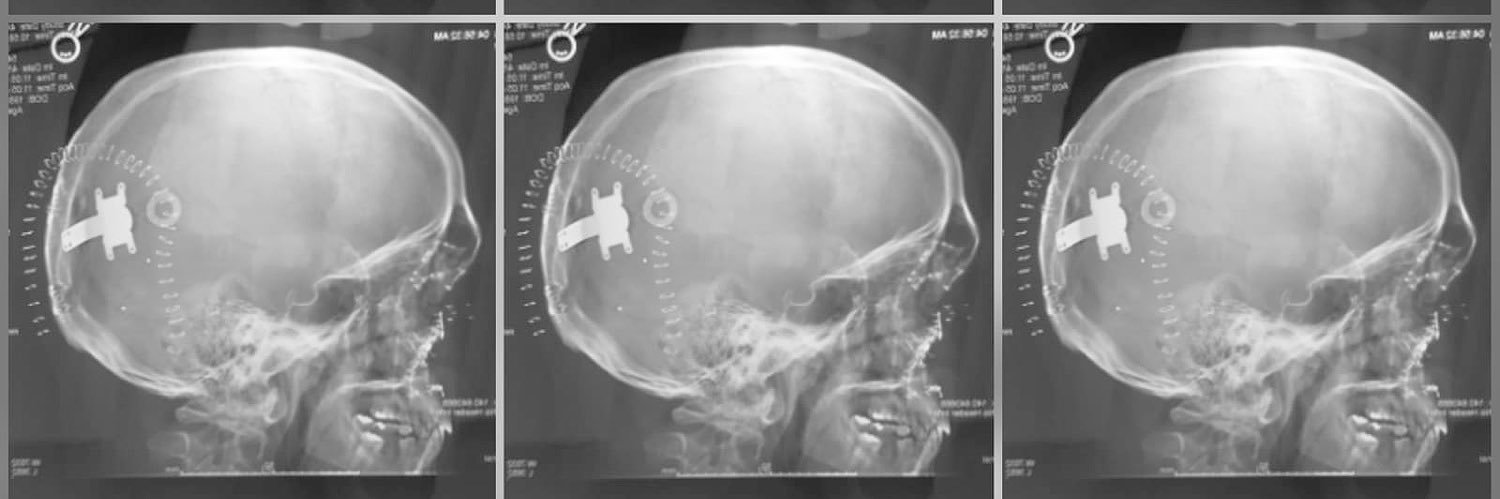

Regaining sight by use of new technology. Participant in the FDA feasibility study for the Orion cortical implant by Second Sight Medical.